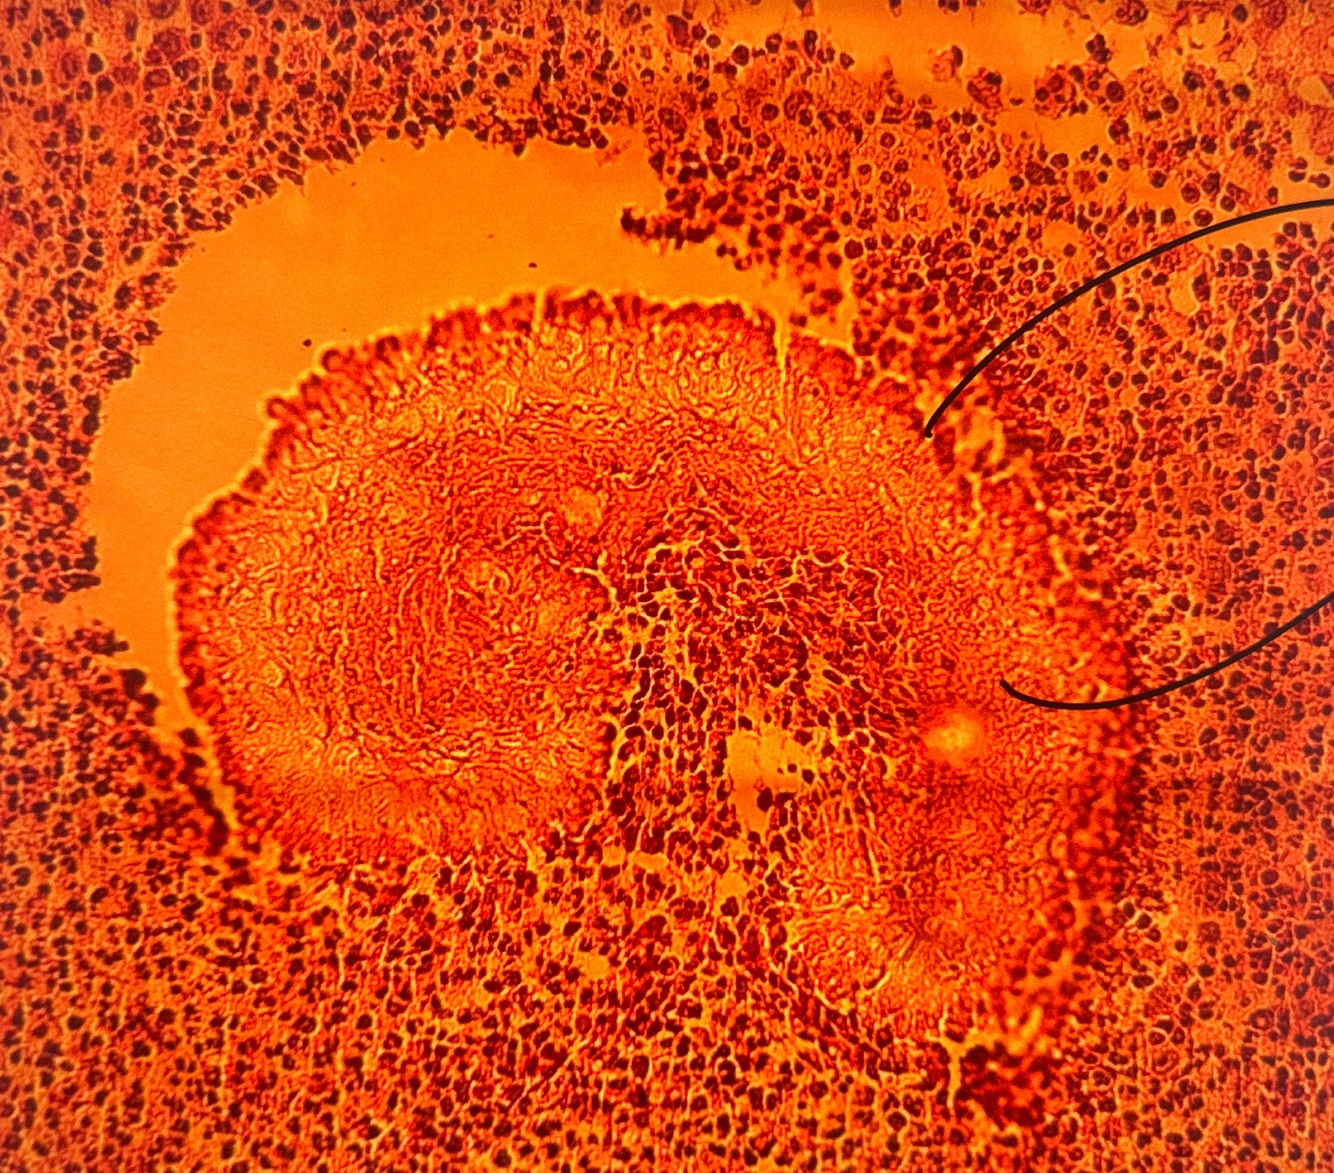

Qual diagnóstico?

Coccidioidomicose